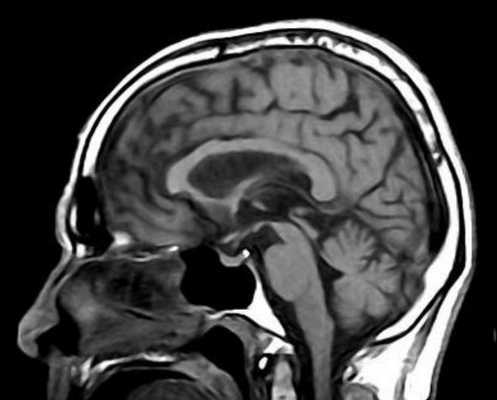

МРТ-исследование проведено на магнитно-резонансном томографе «Siemens» с напряженностью магнитного поля 1,5 Тл, с получением стандартных Т1- и Т2-взвешенных изображений (Т1-ВИ, Т2-ВИ) в фронтальной, аксиальной и сагиттальной плоскостях, с последующей оценкой визуальных изменений головного мозга (см. рисунок). Выявлены признаки атрофии среднего мозга с симптомами колибри в сагиттальной (см. рисунок, а) и Микки Мауса в аксиальной плоскостях (см. рисунок, б).

МРТ головного мозга 79-летней пациентки с ПНП.

а — Т1-взвешенное изображение, сагиттальная плоскость. Атрофия среднего мозга, сохранение объема моста и атрофия крыши среднего мозга. Симптом клюва колибри; б — Т2-взвешенное изображение на аксиальном срезе на уровне среднего мозга. Атрофия среднего мозга с формированием симптома Микки Мауса.

Учитывая прогрессирование заболевания в течение года, с постуральными нарушениями, акинетико-ригидным синдромом, параличом взора, дизартрией, умеренным когнитивным нарушением, стереотипными поведенческими нарушениями, данные МРТ головного мозга (атрофия среднего мозга), а также недавно возникший оромандибулярный гиперкинез на фоне приема противопаркинсонического препарата, выставлен диагноз «ПНП с леводопа-индуцированной дискинезией в виде оромандибулярного гиперкинеза».